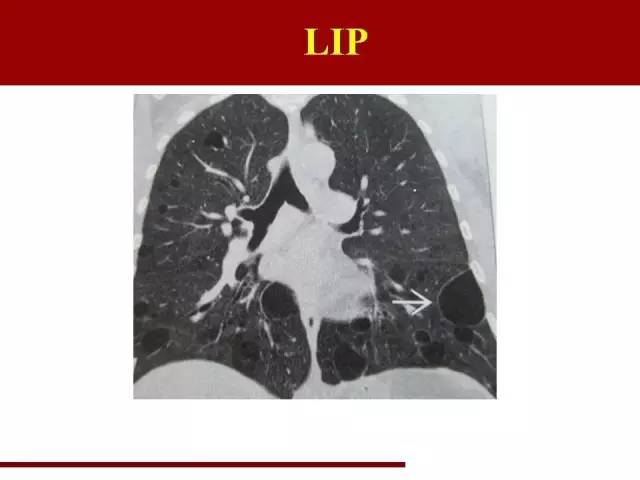

LIP同样是一类疾病的不同阶段,前身是滤泡性细支气管炎

LIP的特点很典型,在幻灯片里已经说过了

袁怀平:

典型的图片,大家一看就能明白